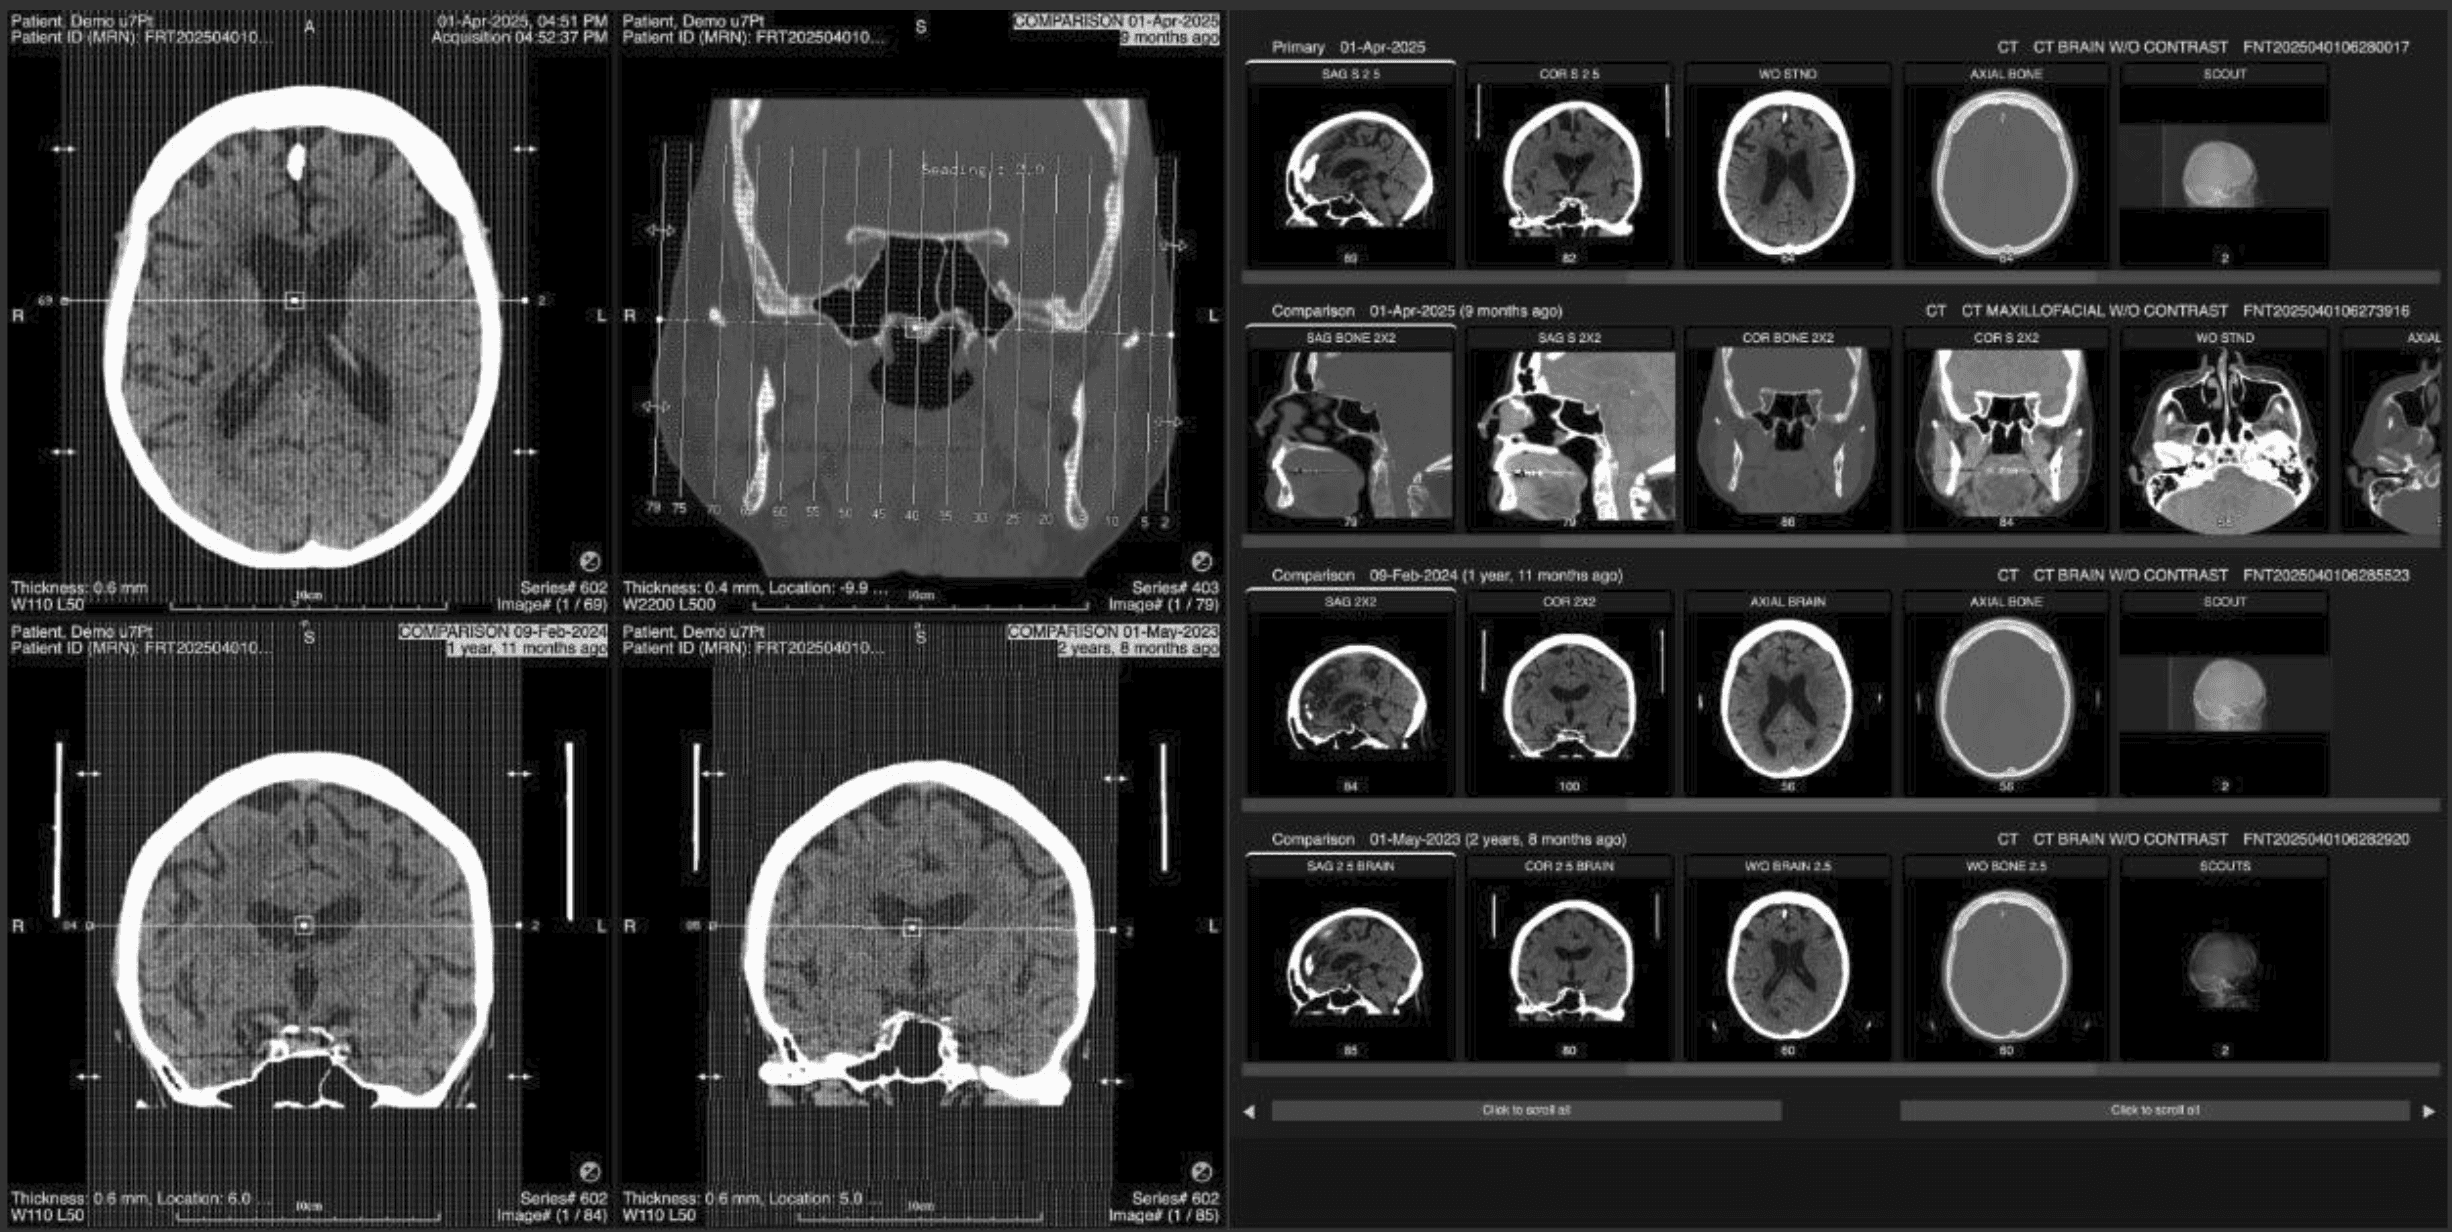

2. Turn Compare Mode on Open a supported exam: CT, MR, PET, NM, US, or XR. Turn Compare Mode on using either: The Compare Mode button in the toolbox or the D keyboard shortcut.

If there is at least one prior, the layout changes to: Left: up to 4 empty viewports. Right: up to 4 thumbnail rows (current + priors).

3. Understand the thumbnail rows and scrolling Each exam has its own row with its own scrollbar. Use the global left and right buttons to move all thumbnail rows together: Single click: move by one thumbnail column. Press and hold: continuous scrolling.

4. Load series into the viewports You can load images into the left viewports in two main ways: Drag and drop (custom layouts). Drag a thumbnail from any row onto a viewport. That viewport shows the selected series from that exam. Repeat in other viewports for any combination you need.

Double‑click a column (aligned layouts) Double‑click any thumbnail column on the right. The series in that column across all rows are loaded into the left viewports: 2 thumbnail rows: 2 filled viewports. 3 thumbnail rows: 3 filled viewports. 4 thumbnail rows: 4 filled viewports.

If a row has no series in that column, its corresponding viewport remains empty.

Which series are considered “in that column” depends on where each thumbnail row’s scrollbar is positioned, plus any global scrolling you have done. |